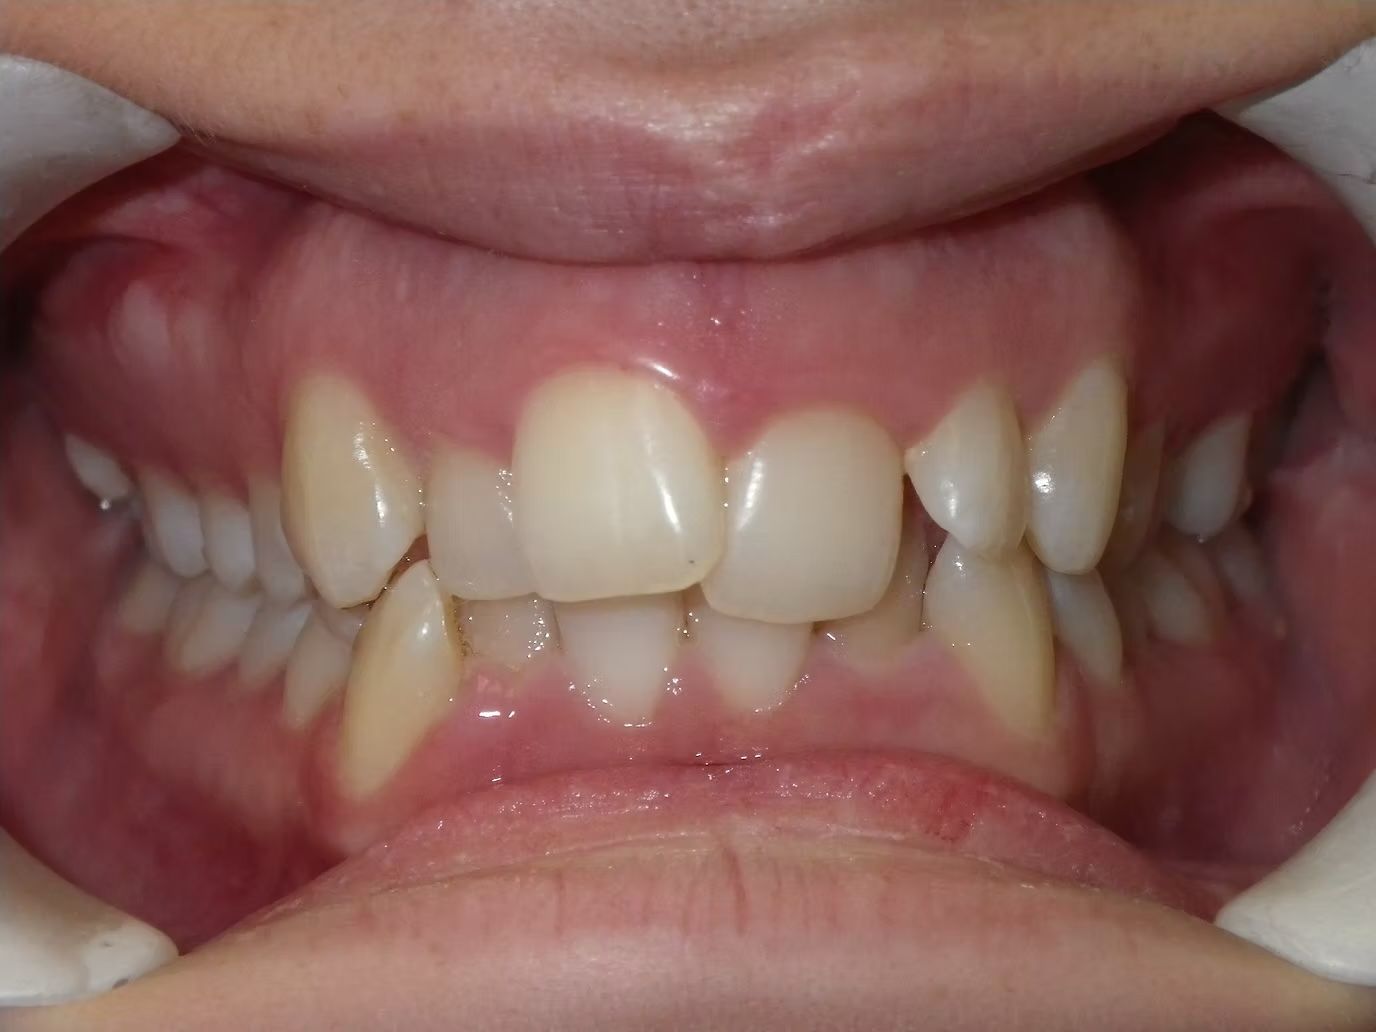

AMBER

Amber, began treatment with Dr. Bret because she didn't like that her front teeth overlapped each other. She had narrow top and bottom dental arches with severe crowding of her upper and lower teeth. She was treated with braces on the upper and lower teeth, and we used the braces to widen the smile. What a change!